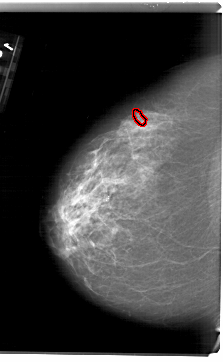

A_1626_1.RIGHT_MLO

FILE: A_1626_1.LEFT_CC.OVERLAY

TOTAL_ABNORMALITIES 1

ABNORMALITY 1

LESION_TYPE CALCIFICATION TYPE PLEOMORPHIC DISTRIBUTION CLUSTERED

ASSESSMENT 4

SUBTLETY 2

PATHOLOGY MALIGNANT

TOTAL_OUTLINES 1

BOUNDARY